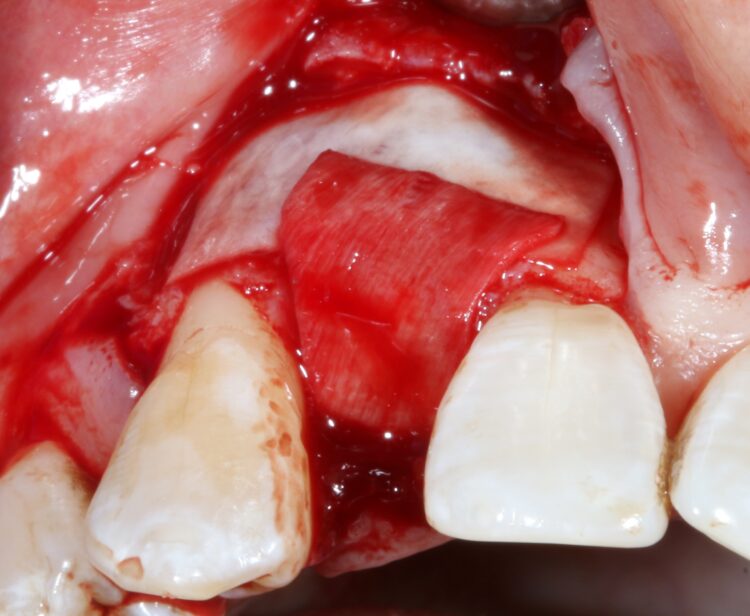

The first treatment phase included the elevation of a large full thickness flap to fully expose the area and enable the harvesting of autogenous bone utilising a safescraper.

The UR2 was then removed including excavation of all granulation tissue, taking care to avoid any direct curettage of the exposed UR3 root. The large bone defect was then filled with a 50/50 mix of autogenous bone chips and an allograft (MinerOss®, a cortico-cancellous mix – BioHorizons Camlog) and the buccal defect was covered with a native porcine collagen membrane with a high percentage of collagen type III for a prolonged barrier function of six months. No fixation pins were used.

The concept was that this exposed membrane would provide a barrier and prevent loss of the bone graft, but would also break down rapidly, favouring early epithelialisation of the open wound by secondary intention healing.

The occlusal aspect of the bone graft – which would remain exposed during the healing period – was covered with a shorter acting native collagen membrane. The concept was that this exposed membrane would provide a barrier and prevent loss of the bone graft, but would also break down rapidly, favouring early epithelialisation of the open wound by secondary intention healing.

The muco-periosteal flap was sutured back with 6.0 Prolene and no attempt was made to coronally advance the flap for complete closure. The rationale was to maintain the open socket wound and thereby preserve the original mucogingival relationship with no alteration. The socket entrance was sealed with the short acting membrane, while the original tooth (after root removal) was utilised as a temporary pontic and bonded to the adjacent teeth with flowable composite.